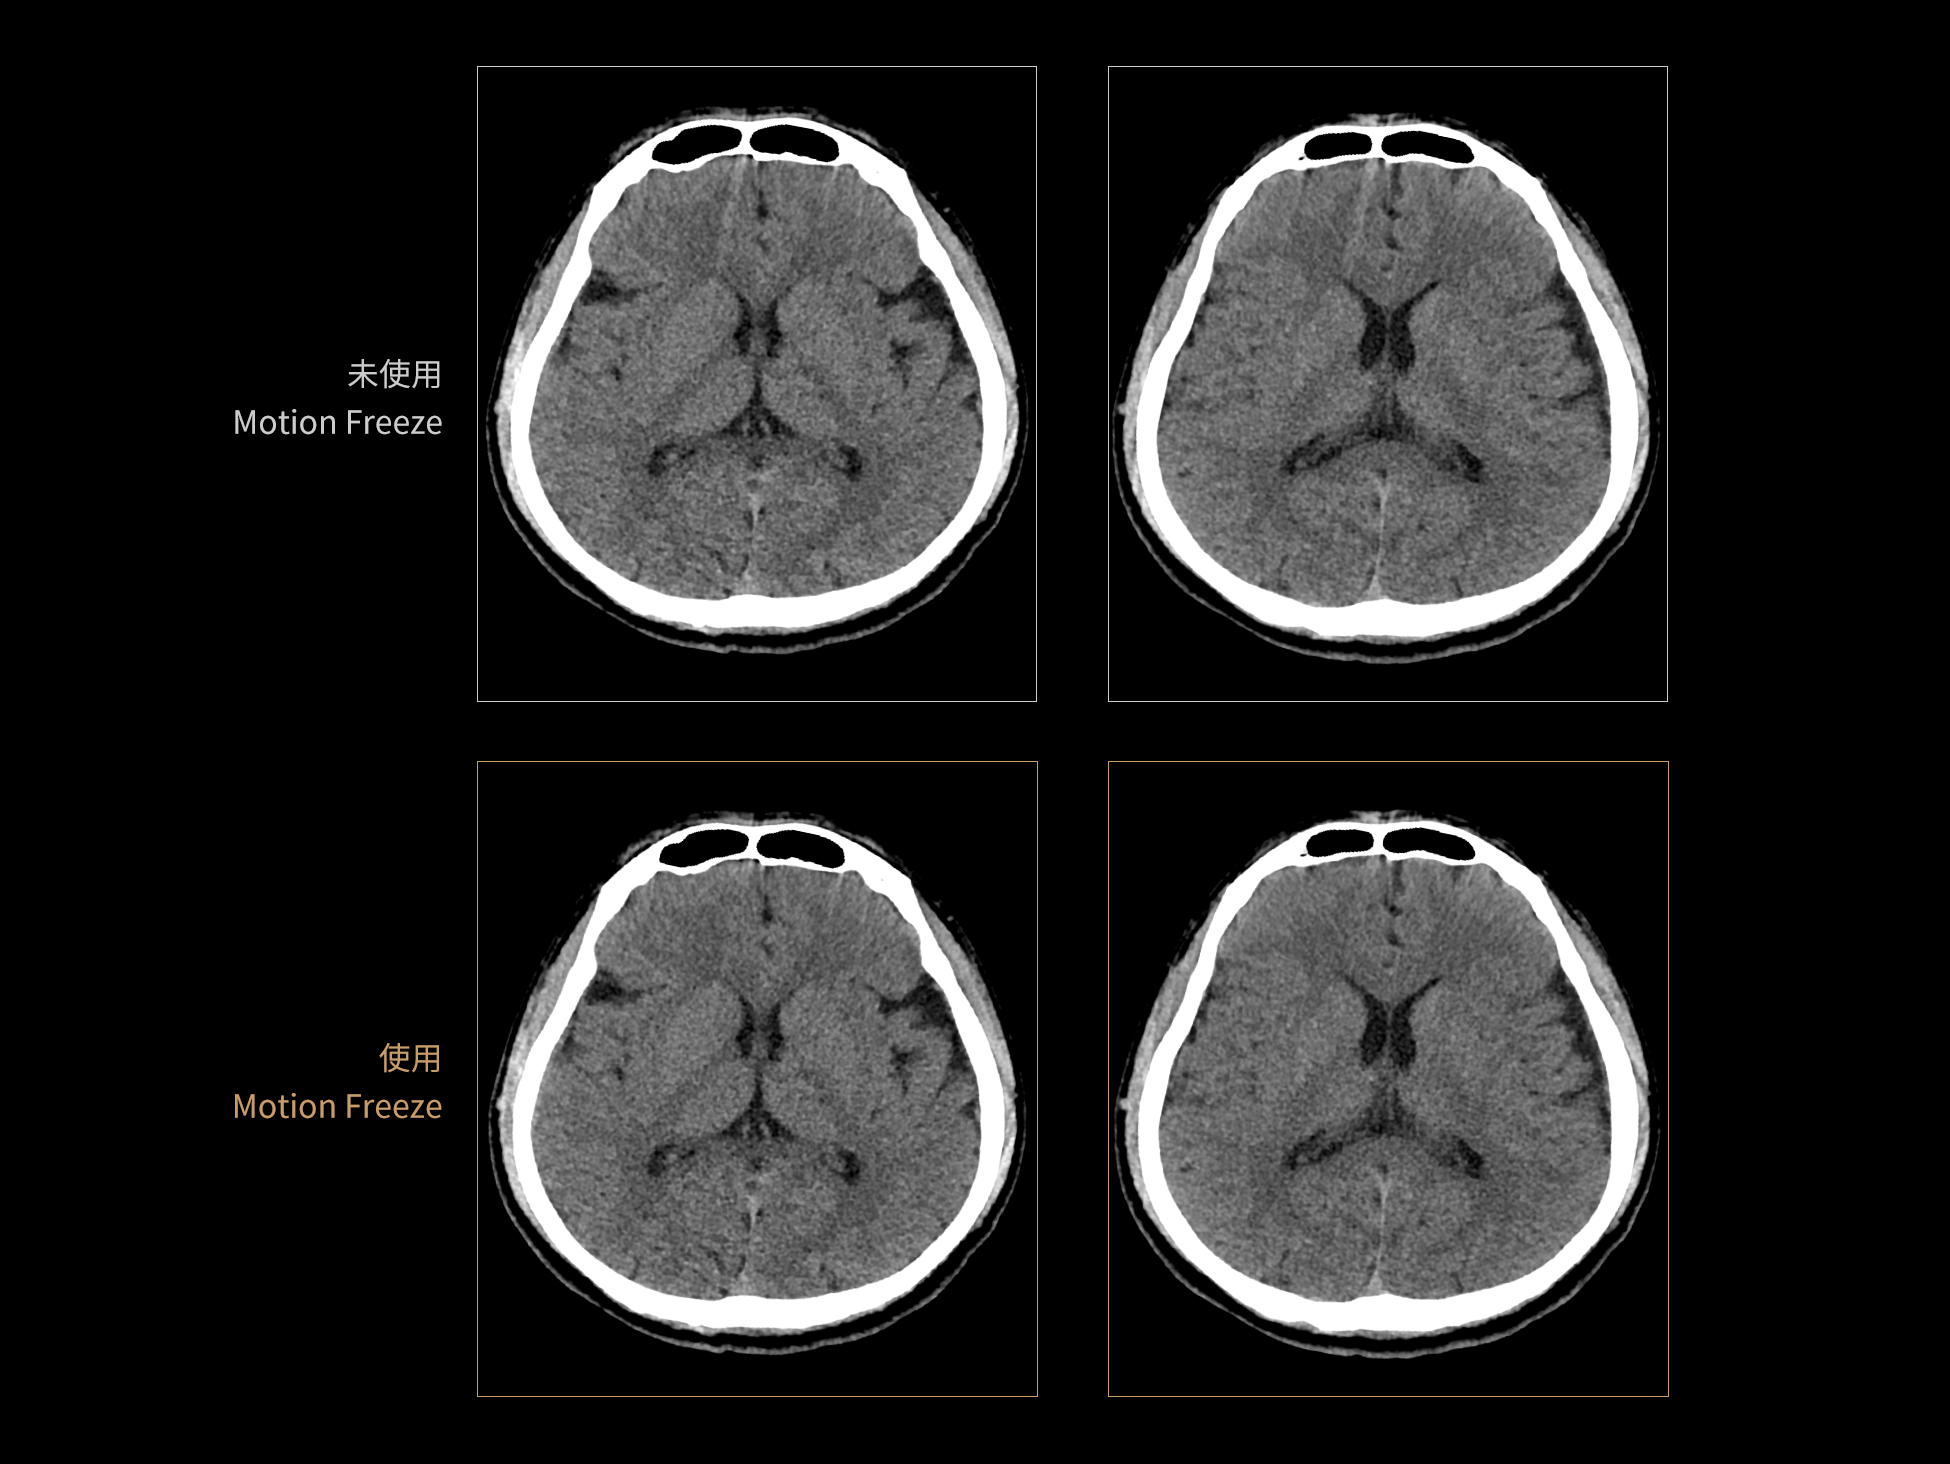

CardioBoost:专属网络设计,重塑心脏影像表现

相同辐射剂量下

低对比度分辨率提升

相同辐射剂量下

空间分辨率提升

相同低对比度分辨率下

辐射剂量减少

相同辐射剂量条件下

图像噪声减少